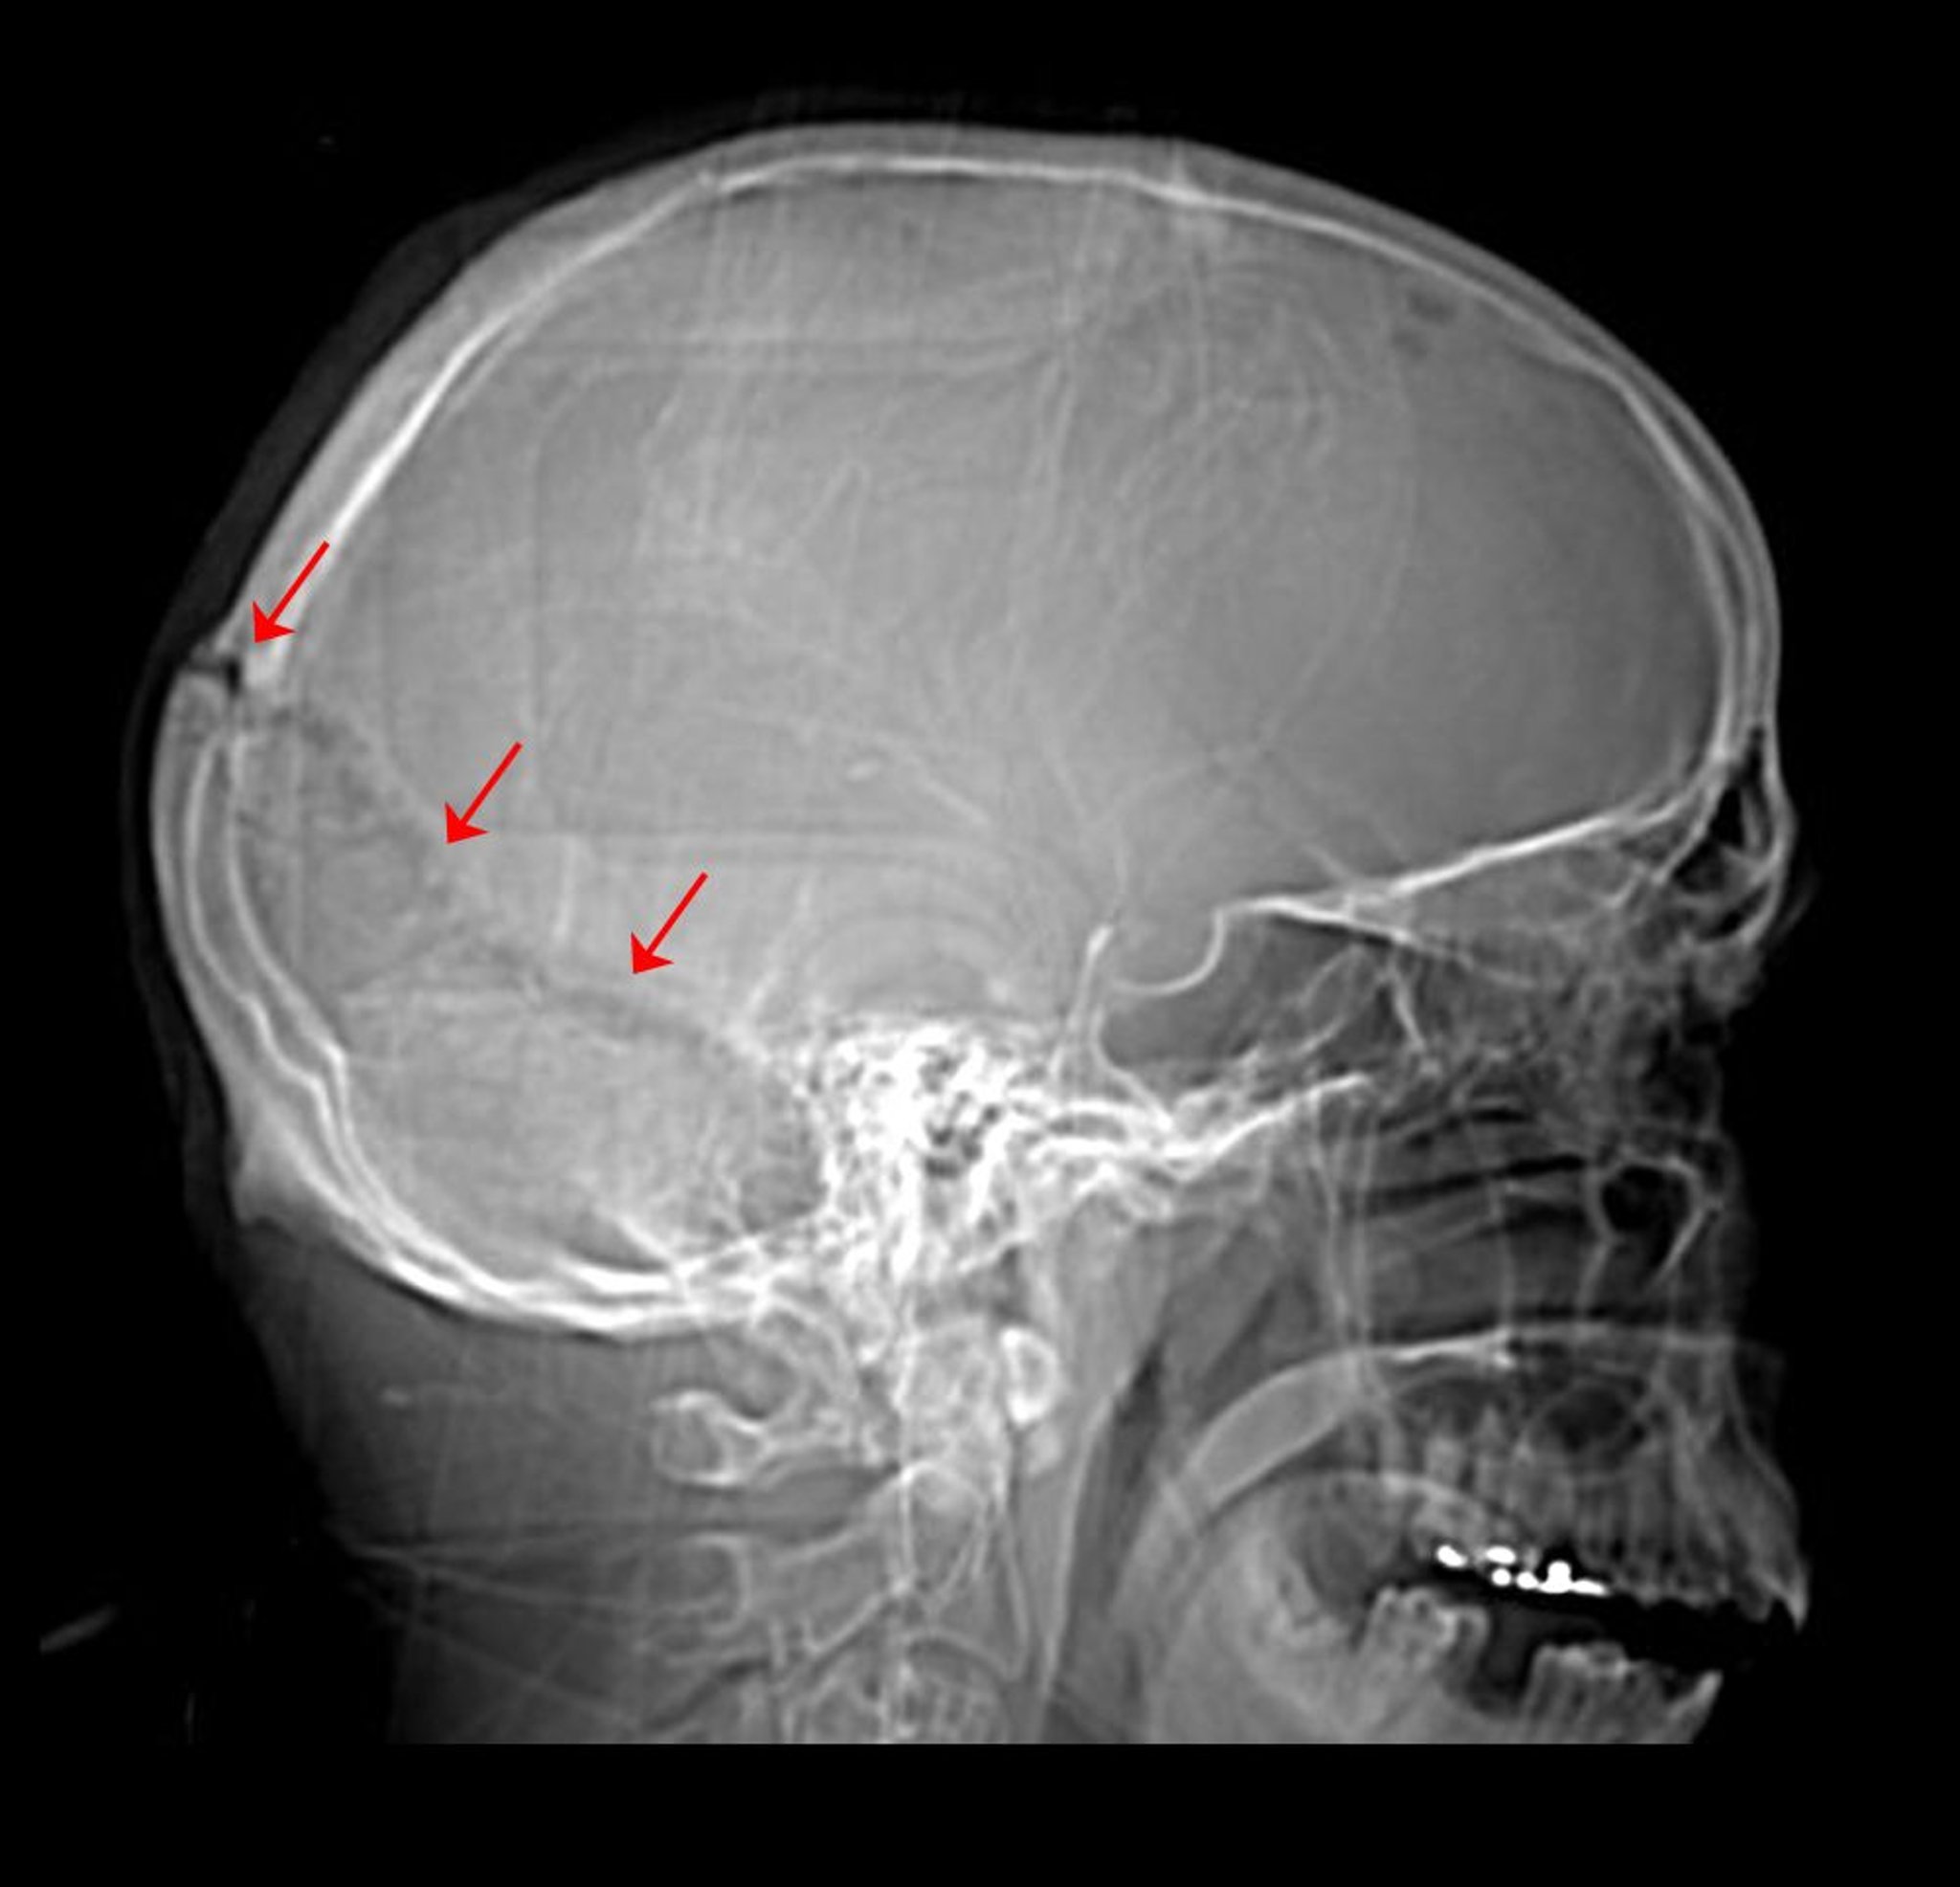

Esta radiografía de cráneo muestra una fractura de la sutura lambdoidea.